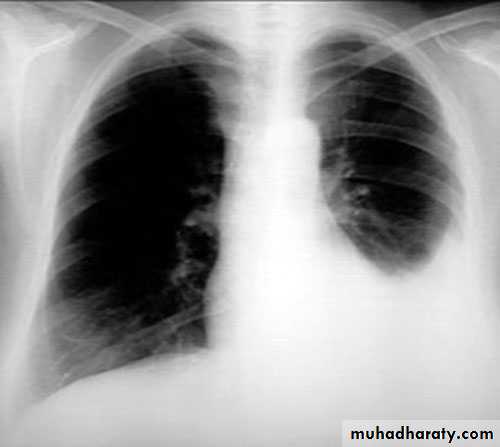

PneumothoraxX-ray pneumothorax

X-ray pneumothorax